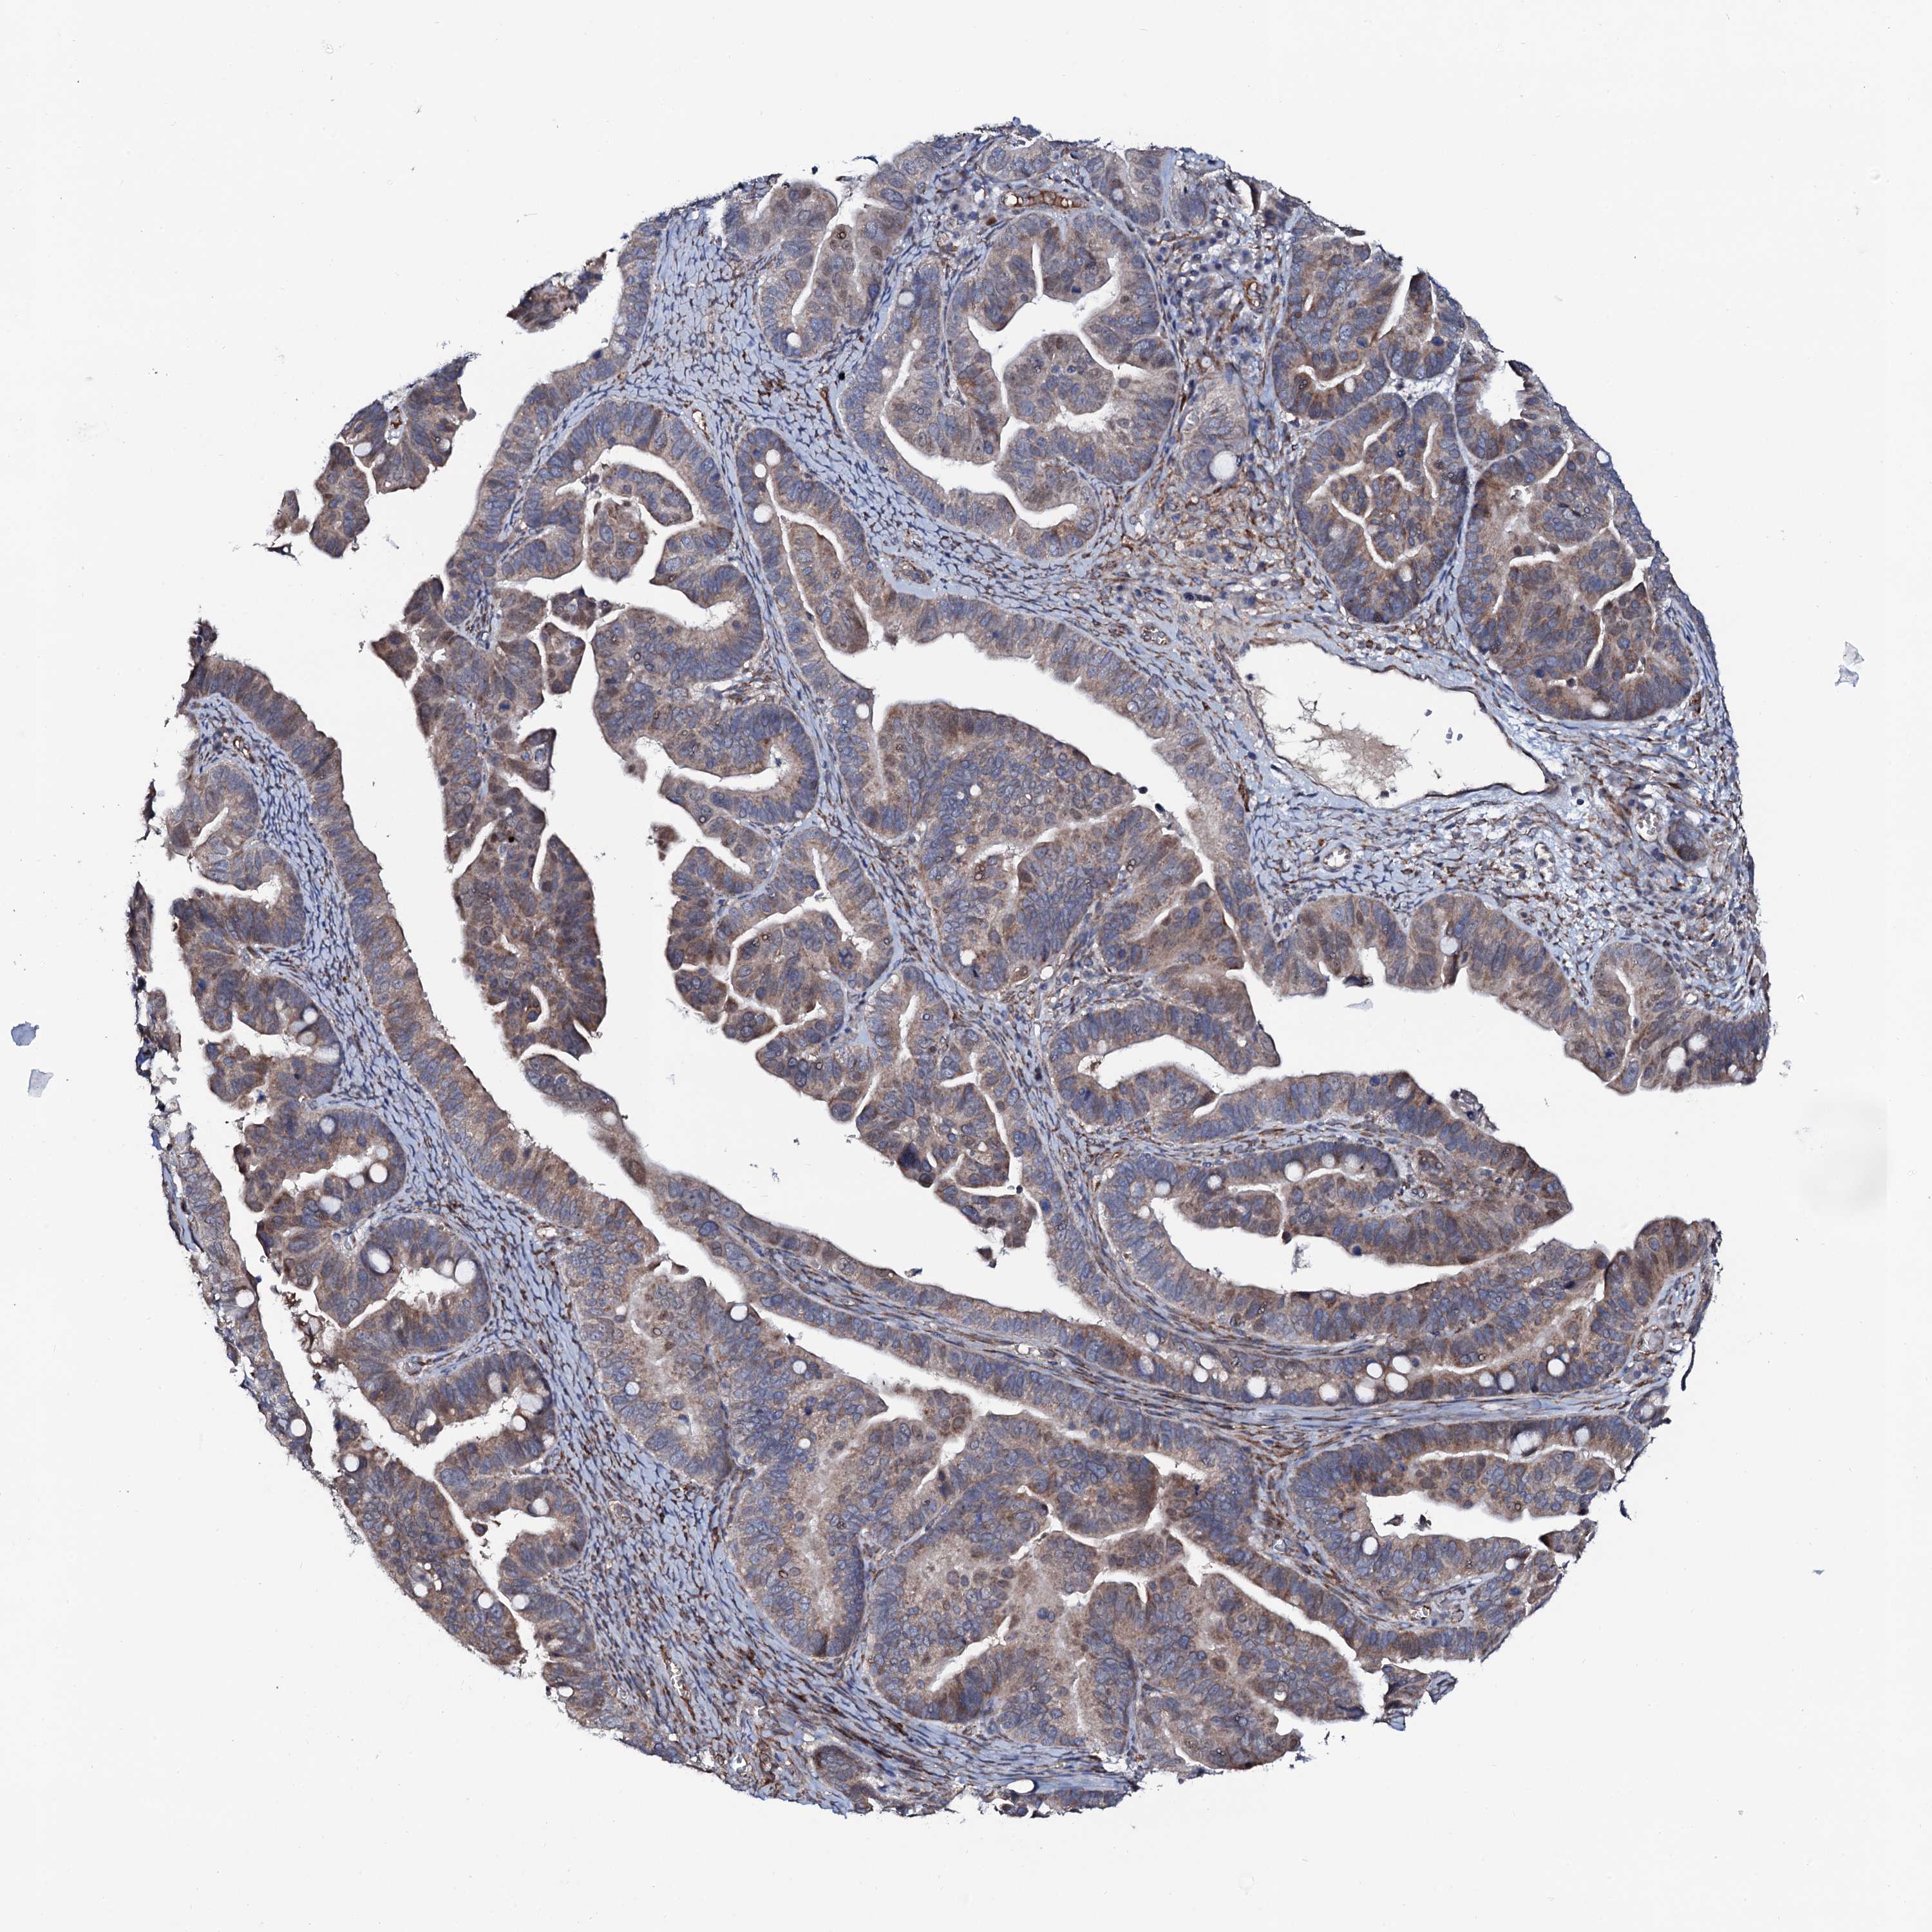

OVARIAN CANCER - Protein expressioni

A mouse-over function shows sample information and annotation data. Click on an image to view it in a full screen mode. Samples can be filtered based on level of antibody staining by selecting one or several of the following categories: high, medium, low and not detected. The assay and annotation is described here.

Note that samples used for immunohistochemistry by the Human Protein Atlas do not correspond to samples in the TCGA dataset.

Antibody stainingi

Antibody staining in the annotated cell types in the current human tissue is reported as not detected, low, medium, or high, based on conventional immunohistochemistry profiling in selected tissues. This score is based on the combination of the staining intensity and fraction of stained cells.

Each image is clickable and will lead to virtual microscopy that enables deeper exploration of all samples and also displays staining intensity scores, fraction scores and subcellular localization as well as patient and tissue information for each sample.

Antibody HPA041146

Staining

High

Medium

Low

Not detected

Intensity

Strong

Moderate

Weak

Negative

Quantity

>75%

75%-25%

<25%

None

Location

Nuclear

Cytoplasmic/membranous

Cytoplasmic/membranous,nuclear

Cystadenocarcinoma, serous, NOS

Carcinoma, endometroid

Cystadenocarcinoma, mucinous, NOS

Carcinoma, NOS